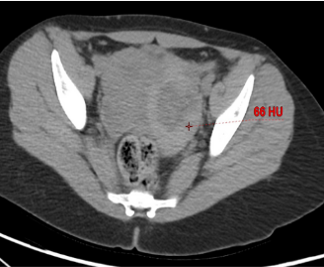

Clots tend to form first near the site of bleeding -thus, the identification of a heterogeneous and relatively higher attenuation clot allows localization of the site of hemorrhage - SENTINEL CLOT SIGN

On contrast-enhanced CT - active hemorrhage- usually serpiginous high-attenuation foci nearly isodense to adjacent vessels.